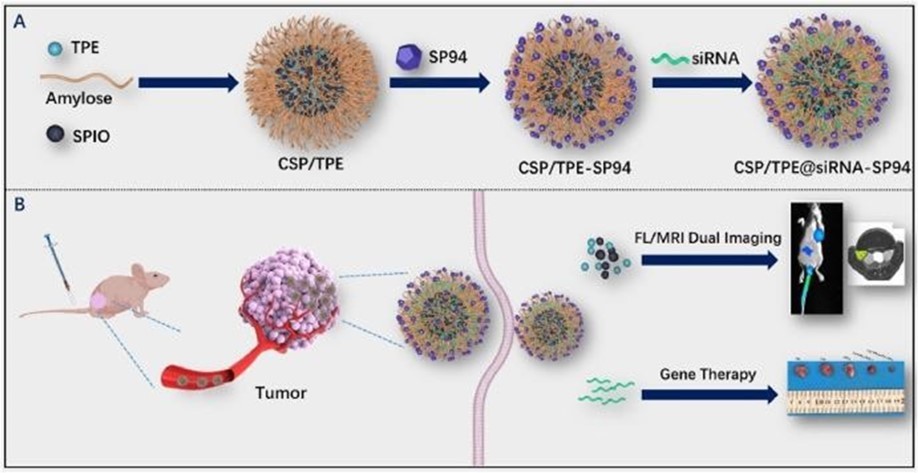

It is a non–invasive method. It can be used to monitor the chemical changes of tissues. We can simultaneously evaluate several metabolites. Two examples of where MRS is very helpful in the brain: The invasion of the tumor (Glioblastoma multiform (GBM) into the surrounding tissues, which is not clear in normal T2 images, but can be determined by MRS. By MRS, it is possible to distinguish two types of lesions that look similar to each other in normal MRI images (such as tumor recurrence and tumor necrosis after radiotherapy). MRS imaging has found wide applications in the field of cancer diagnosis. Among the fields of clinical application of MRS, we can mention the diagnosis (between normal and cancerous tissue, different types of cancer and neoplastic from non–neoplastic), designing the best treatment regimens for each patient, and monitoring the patient after treatment. MRS in tumors: In brain tumors, spectroscopy can determine the degree of malignancy. As malignancy increases, NAA and creatine decrease and choline, lactate and fat increase. Fat is seen in the necrotic parts of the tumor. Lactate concentration increases in rapidly growing tumors due to anaerobic glycolysis. Diagnosing tumor recurrence from the effects of radiotherapy: Increased choline is a marker for tumor recurrence. Changes due to radiotherapy usually decrease NAA, creatine and choline. If necrosis has occurred as a result of radiotherapy, fat and lactate can also be seen in the spectrum. Molecular imaging using spectroscopy Cerebral ischemia and infarction: When the brain suffers from ischemia, anaerobic respiration of glucose is used and lactate increases. Choline increases and NAA and creatine decrease. If it happens after ischemia, the fat signal is also seen. trauma: It is a useful method to assess the degree of nerve damage and predict the results. The clinical consequences are opposite to the NAA/Cr ratio, and the observation of lactate and fat indicates the seriousness of the condition. infectious diseases: decrease naa Inside the abscess, lactate, alanine, cytosolic acid and acetate increase. Alzheimer: In the advanced stages of Alzheimer's, NAA decreases and myo–inositol increases. MS: The increase of choline and lactate has shown that the increase of choline can be due to the increase of phospholipid as a result of breaking the myelin of the cell and the increase of lactate is due to the increase of the anaerobic respiration of the cell due to the increase of the cell metabolism. In addition, there is evidence of increased lipids, and most importantly, decreased NAA, which is caused by nerve damage. And recently, it has been found that glutamate and myoinositol levels increase in acute MS lesions. Parkinson: In most studies in Parkinson's disease, no changes in metabolites have been observed, only when Parkinson's has caused brain atrophy, a decrease in NAA in the basal ganglia has been observed (Figure 3, Figure 4, Figure 5, Figure 6).

Figure 5.Schematic of different steps of CERN Large Hadron Collider (LHC) radiation source for magnetic resonance biospectroscopy in metabolic and molecular imaging and diagnosis of cancer.